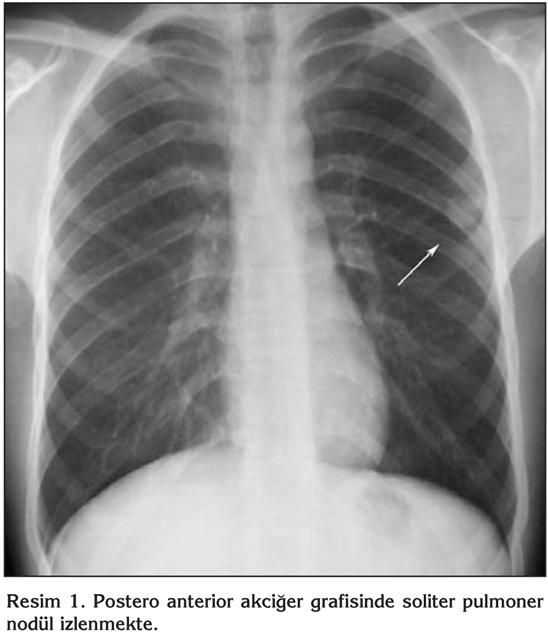

Yirmi ya??nda erkek hastan?n, alt? ayd?r halsizlik ve ?? ayd?r sol yan a?r?s? yak?nmalar? vard?. Askerlik g?revini yapmakta iken Verem Sava? Dispanseri taraf?ndan yap?lan taramada ?ekilen PA akci?er grafisinde ku?kulu lezyon saptanmas? ?zerine hastanemize sevk edildi. Fizik muayene bulgular? normal saptand?; hastan?n ate?i; 36?C, nabz?; 63 vuru/dakika, TA; 100/65 mmHg, solunum say?s?; 16/dakika idi. ?z ge?mi?inde ve yak?n aile anamnezinde bir ?zellik yoktu. Bir paket/y?l sigara ?yk?s? vard?. Tam kan, tam idrar, sedimentasyon ve rutin biyokimya incelemeleri normal s?n?rlarda tespit edildi. PA ve lateral akci?er grafilerinde sol hemitoraksta ?st zonda SPN ile uyumlu g?r?n?m mevcuttu (Resim 1,2). Toraks bilgisayarl? tomografi (BT)'de; sol akci?er ?st lob apikoposterior segmentte, periferik yerle?imli, yakla??k 2 x 2 cm ?ap?nda, d?zg?n kont?rl?, sferik SPN ile uyumlu g?r?n?m saptand?. Mediastende patolojik boyutlarda lenfadenopati yoktu ve tan?mlanan g?r?n?m haricinde infiltrasyon ve kitle saptanmad? (Resim 3). Hasta balgam ??karamad??? i?in al?nan mide suyu asido-alkalo rezistan basil (ARB) negatif olarak de?erlendirildi ve k?lt?r?nde ?reme olmad?. Bronkoskopide endobron?iyal lezyon g?zlenmedi. Bron? lavaj? ARB negatifti ve k?lt?r?nde ?reme olmad?. Bron? lavaj? sitolojik incelemesi malignite y?n?nden negatif olarak raporland?. Kist hidatik i?in yap?lan ELISA testi negatif bulundu. Bat?n ultrasonografi (USG) incelemesi normaldi. Olgudan SPN etyolojisini ayd?nlatabilmek i?in g???s cerrahisi kons?ltasyonu al?nd? ve olguya kist hidatik ?n tan?s?yla operasyon planland?. Torakotomi ile sol ?st lobda saptanan 2 x 2 cm'lik nod?le wedge rezeksiyon uyguland? ve perioperatif patoloji kons?ltasyonu istendi. Elde edilen materyalin makroskobik incelenmesinde malignite saptanmamas? ?zerine operasyon sonland?r?ld?. Eksizyonel biyopsi ?rne?inin mikroskobik incelemesi intralober pulmoner sekestrasyon (Kesitlerde akci?er parankimi bulgular? g?steren iyi s?n?rl? nod?ler lezyon izlenmektedir. G?m??leme y?ntemiyle yap?lan incelemede lezyonda yayg?n olarak retik?lin liflerinde art??, baz?lar? hiperplastik g?r?n?mde damar yap?lar? ve d?zensiz bron? alveol ?at?lar? g?r?lmektedir) olarak raporlanm??t?r.

Resim 1